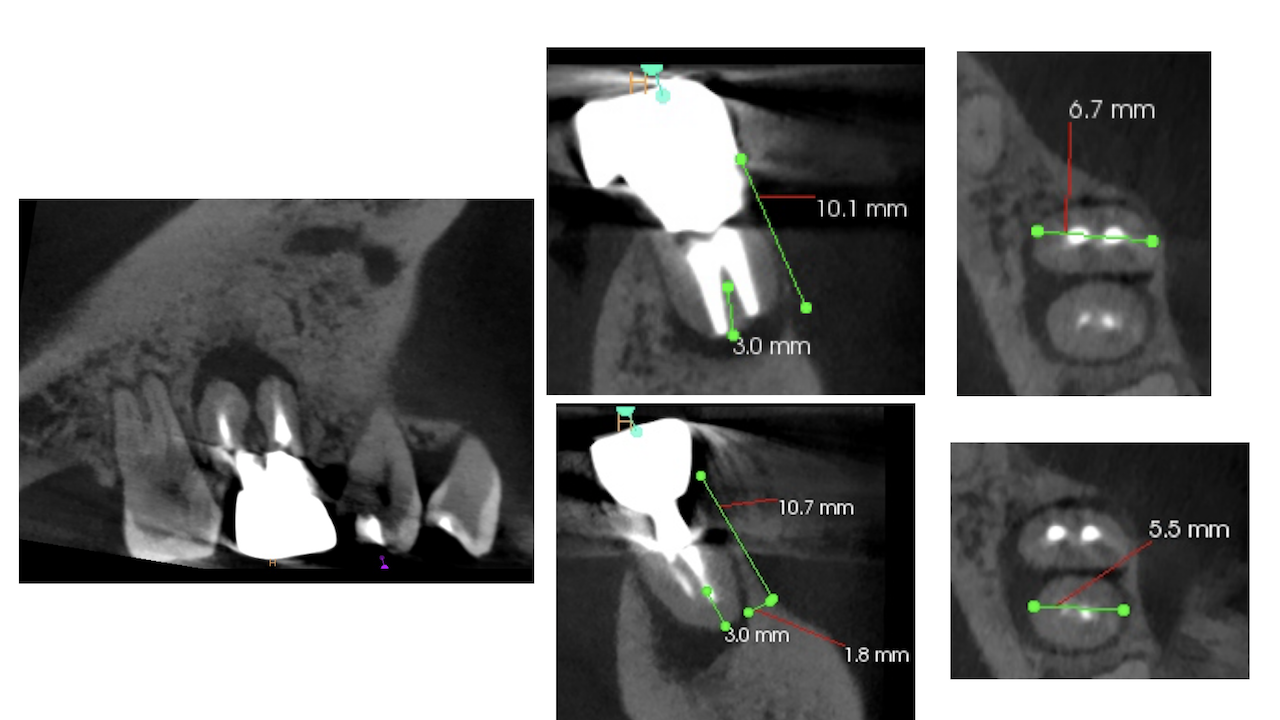

#19 M,D Apicoectomy(2024.9.19)

MのApexはその位置がはっきりと見える。

Apexから3mmを6.7mmの頬舌的な幅で切断し、逆根管形成した。

逆根管充填した。

次がDだ。

ここはOsteotomyが必要である。

DのApexを見つけて根切し、逆根管形成、逆根管充填した。